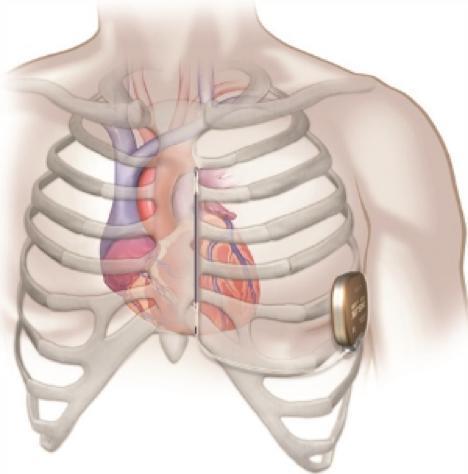

心脏性猝死(sudden cardiac death,SCD)是心血管病死亡的首要原因,植入型心律转复除颤器(ICD)是目前最为有效的预防SCD的治疗手段。传统的经静脉植入型心律转复除颤器(transvenous ICD,TV-ICD)由于经静脉植入的特点,除颤导线相关的短期和长期并发症不容忽视。皮下植入型心律转复除颤器(subcutaneous ICD,S-ICD)为减少或避免TV-ICD并发症而设计,是第一个不在心腔内植入导线而具有感知和除颤功能的心脏电子器械,也是预防和降低SCD风险的一种新方法,其操作相对简单,导线相关并发症较TV-ICD明显减少,且有效性和安全性得到了证实。2016年在中国正式应用以来,临床上越来越多猝死高风险患者接受了S-ICD植入。截止目前全球已植入突破10w例。无触心,更自由!

SICD适应症指南

S-ICD的脉冲发生器和导线均植入皮下、不接触心腔,但能提供电击后7.5ms脉宽、200mA输出,最长30s起搏。2015ESC第一次将S-ICD写入指南:“对于无需起搏、CRT或ATP治疗的ICD适应证患者,S-ICD应当被考虑作为经静脉ICD的替代治疗”。目前《2017年AHA/ACC/HRS室性心律失常和心脏性猝死指南》对于存在ICD植入指征,且没有足够的静脉通路或高感染风险,同时不需要也预期不需要心动过缓起搏或终止室性心动过速起搏或心脏再同步治疗的患者,推荐植入S-ICD(推荐级别I类);对于存在ICD植入指征,同时不需要也预期不需要心动过缓起搏或终止室性心动过速起搏或心脏再同步治疗的患者,推荐植入S-ICD是合理的(推荐级别IIa)。2021年《植入型心律转复除颤器临床应用中国专家共识》也参考了该指南。